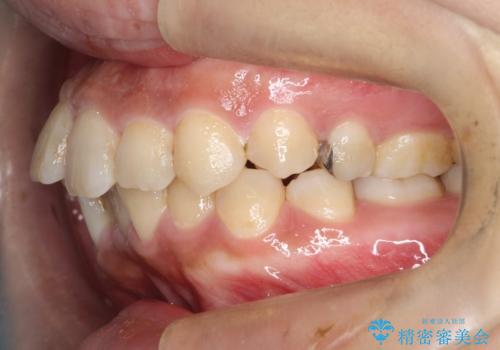

- 主訴:学生時代に矯正治療したが、後戻りしてしまった。上下前がのガタつきを治したい。

ワイヤー矯正(審美装置)非抜歯 治療期間:1年8か月

途中、大臼歯の遠心移動のためリンガルアーチを使用しています。